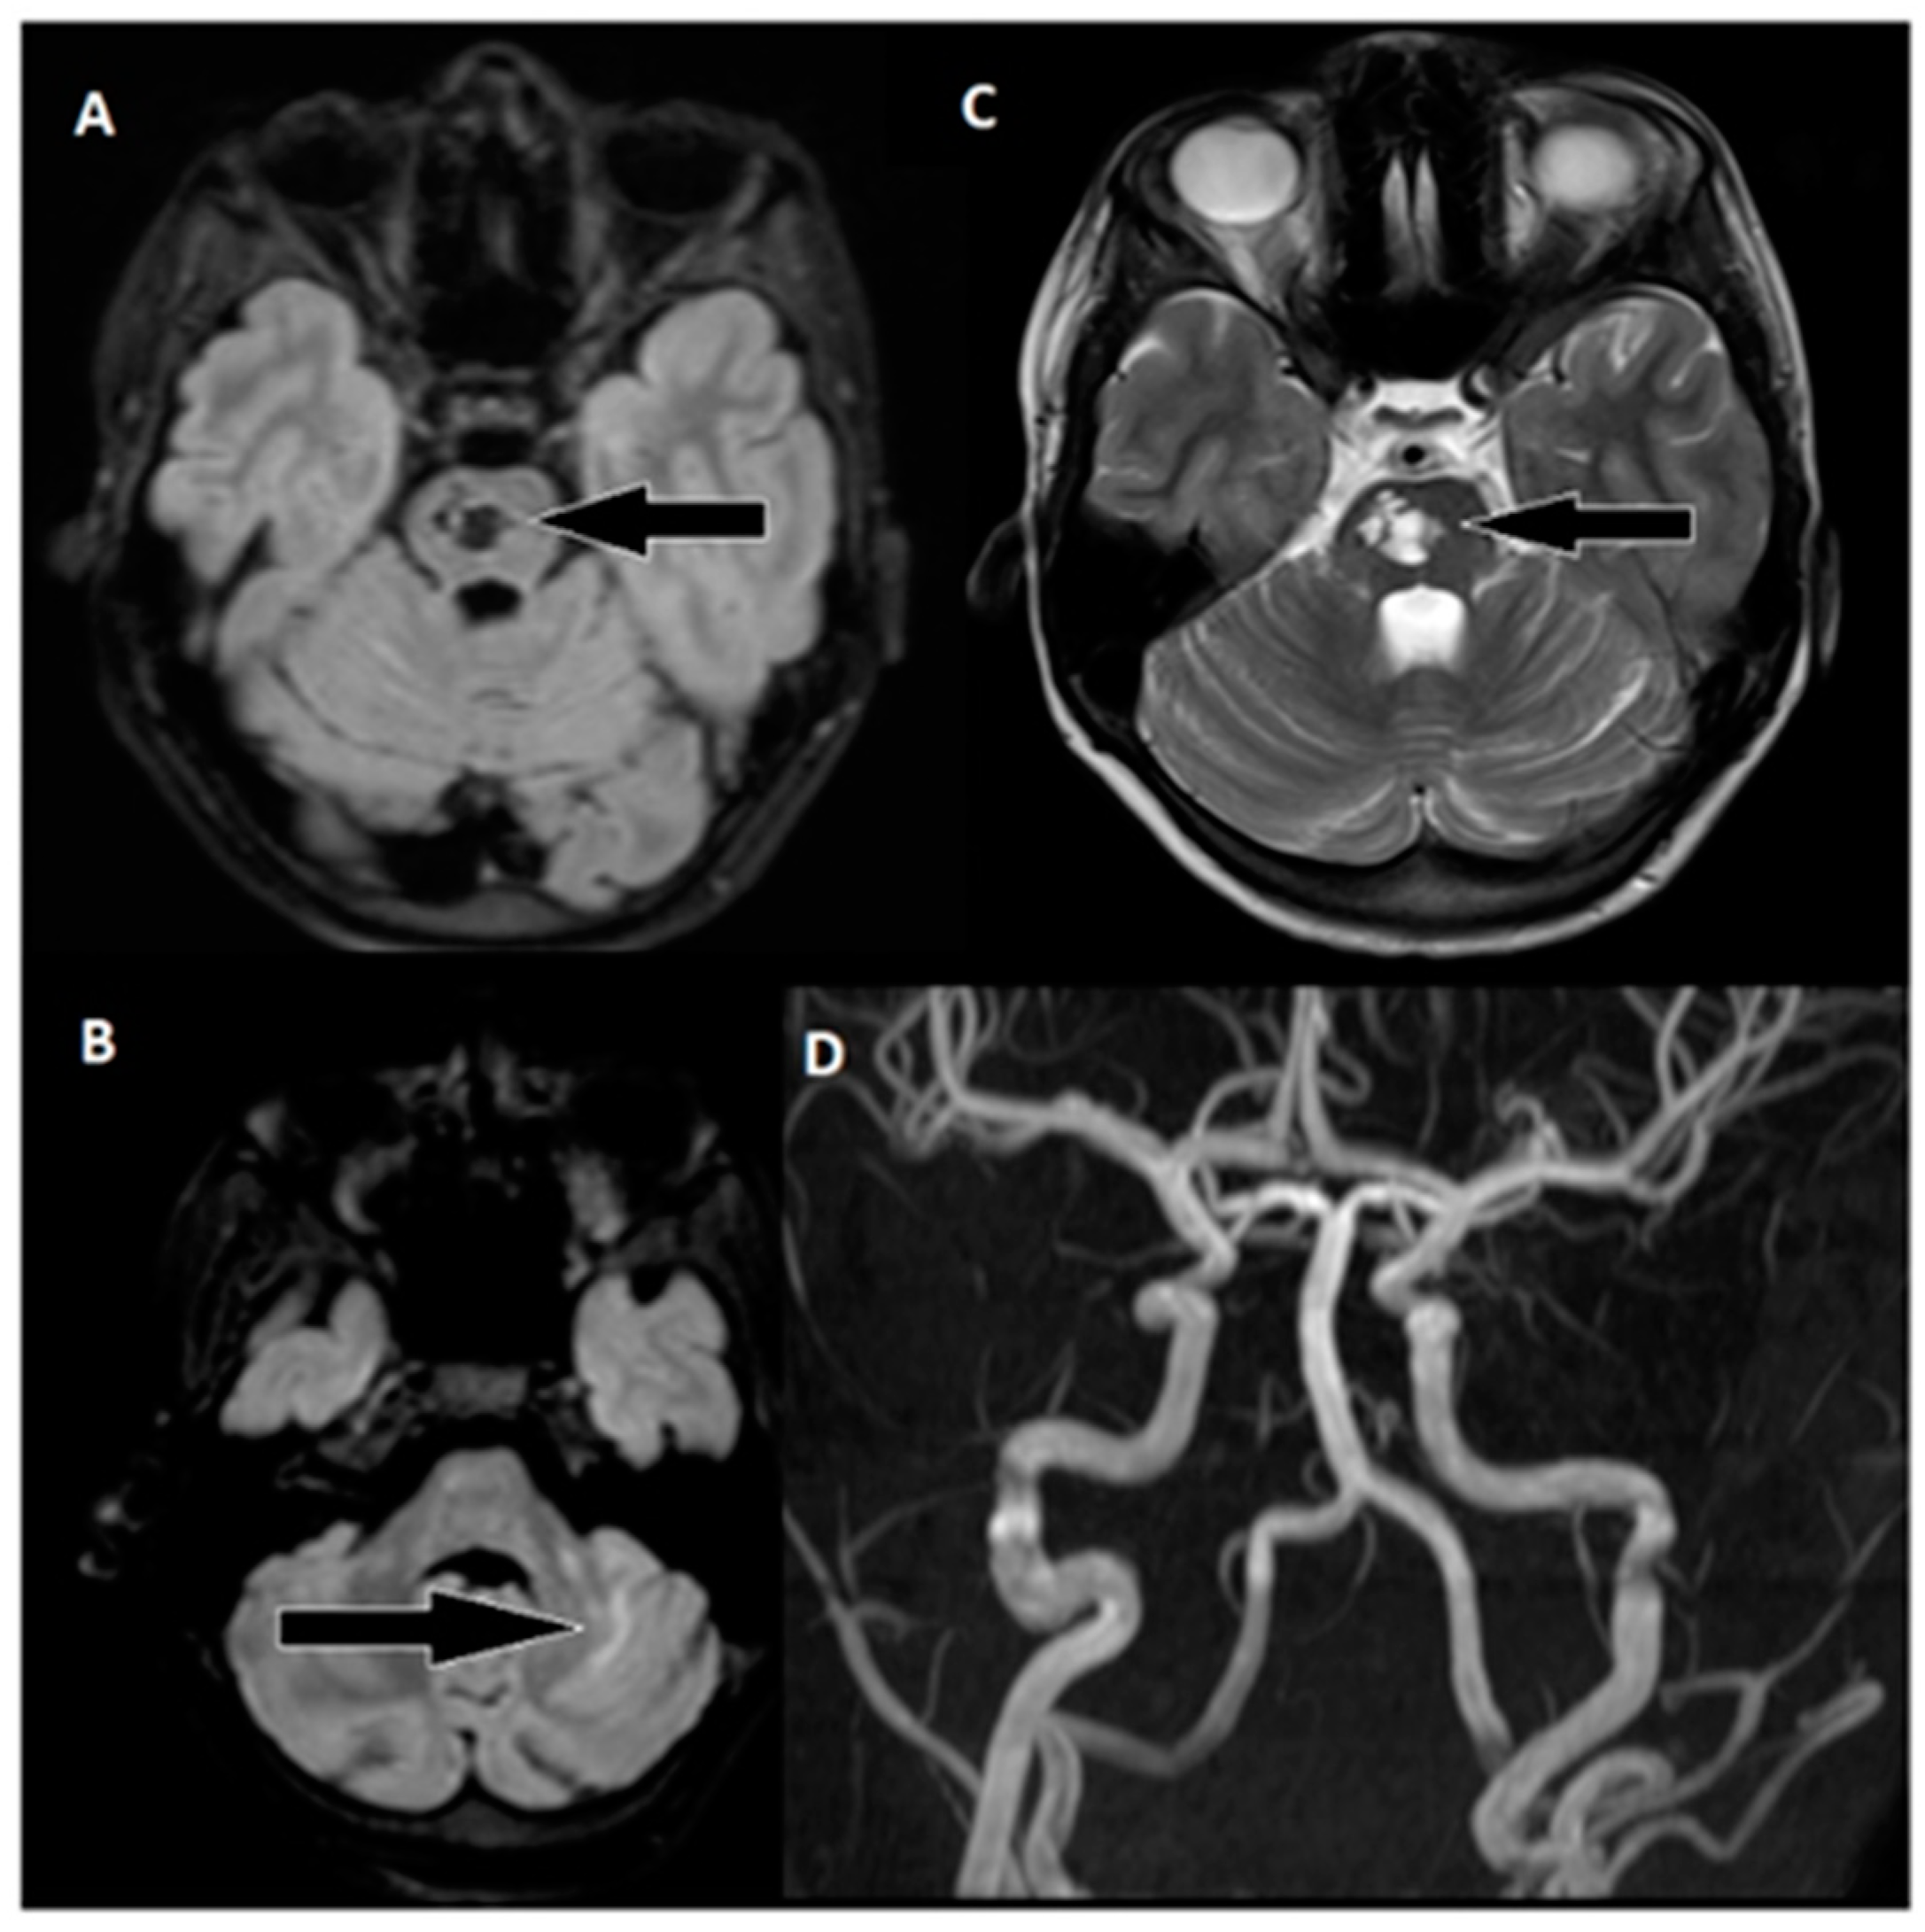

A 9-year-old male was admitted to a regional hospital due to a persistent complaint of diarrhea, exceeding ten episodes in two days, accompanied by a single episode of vomiting, tension headache, and mild vertigo. Initial diagnostic assessments did not reveal any notable abnormalities, leading to a diagnosis of gastroenteritis. Following rehydration therapy, the patient’s overall condition improved, and discharge plans were being considered. However, on the subsequent day after admission, at approximately 6 pm, the patient suddenly experienced weakness localized to the left side of his body. Recognizing the urgency of the situation, an emergency consultation with a neurologist was promptly arranged. Two hours following the onset of these new symptoms, a computed tomography (CT) scan of the brain was conducted (Figure 1), which did not show any acute changes in the brain. Nevertheless, the CT scan did reveal two hypodense regions in the left cerebellum, which raised suspicion of malignancy, along with a hyperdense appearance of the basilar artery (BA). Additionally, a hypodense region was noted in the left thalamic region, suggesting a potential prior lacunar stroke.

Figure 1. Emergency CT scan of the brain. (A) Hypodense region in the left thalamic region; (B) hyperdense basilar artery (HDBA) sign; (C) 2 hypodense regions in the left cerebellum.